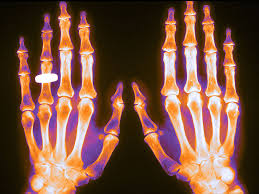

Rastreo para prevención de las fracturas por fragilidad: guía de Canadá

Para personas sin tratamiento preventivo actual de fracturas, la estrategia de realizar primero la evaluación del riesgo con la herramienta FRAX en mujeres de 65 años o más facilita la toma de decisiones compartida y permite a las pacientes considerar la farmacoterapia preventiva dentro de su contexto de riesgo individual (antes de la densitometría). La recomendación contra la detección en hombres y mujeres más jóvenes enfatiza la importancia de la buena práctica clínica. Canadian Medical Association Journal, 8 de mayo de 2023.